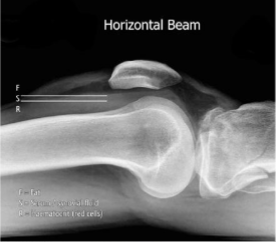

What is this and what type of scan

fat fluid level, x-ray